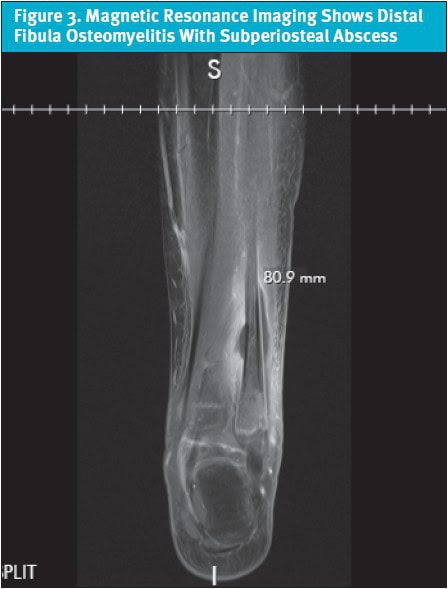

At the hospital, the patient was given morphine and ondansetron. Ultrasound (US) of the right lower extremity was significant for cellulitis and fluid collection. The patient was started on empiric IV antibiotics, and orthopedics was consulted. Magnetic resonance imaging (MRI) showed distal fibula osteomyelitis with subperiosteal abscess, and the patient was taken to surgery (Figure 3). Following surgical debridement, IV antibiotics were administered for 5 days.

MRI is the modality of choice for diagnosis of acute osteomyelitis with a sensitivity between 80-100%.14,19 It has limitations including cost, availability, time constraints, and the need for sedation in young children. MRI identifies osseous involvement, surrounding soft tissue infection, and septic arthritis and helps to distinguish between noninfectious causes of clinical symptoms.[21] MRI also identifies patients with indications for surgery or invasive procedures. This is important in the setting of more aggressive MSSA and MRSA infections.10